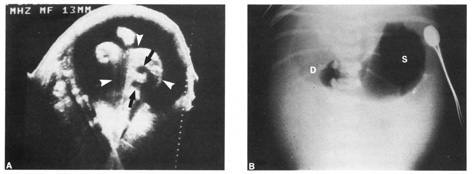

A second trimester ultrasound is usually done at 20 to 22 weeks' gestational age. The most commonly used fetal measurements are biparietal diameter, length of the femur or other long bones, and abdominal and head circumference. In addition to measurements, an anatomic survey is also done to evaluate the fetal brain (Fig. 9), spine, stomach, heart, kidneys, placental location and assessment of amniotic fluid (Fig. 10). If maternal risk factors are present, tetra screening results are abnormal, or there are abnormal findings on the anatomic survey, the patient is sent for a comprehensive ultrasound. The components of a comprehensive ultrasound are shown in Table 9. The ultrasound findings associated with Down syndrome include cardiac defects or enlargement, cystic hygroma (Fig. 11), duodenal atresia (Fig. 12), omphalocele, polyhydramnios, choroids plexus cyst, and renal calyceal dilation.

Fig. 12. Duodenal atresia in a second trimester fetus. A: Ultrasound scan of fetal abdomen (arrowheads) showing two fluid-filled structures (arrows). Increased amniotic fluid (polyhydramnios) surrounds the fetus. B: Newborn radiograph of upper abdomen demonstrating gas-filled stomach (S) and duodenum (D), which are typical findings of duodenal atresia. (Courtesy of Alfred B. Kurtz, MD)